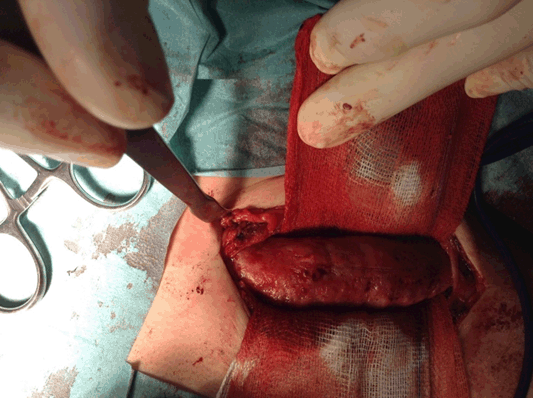

This is a case of an 11-year-old boy with left clavicle pain with two months of evolution presented to emergency department. No history of trauma, fever or systemic signs, recent illness and no relevant personal or familiar medical history. No neurological or vascular abnormalities were found in the upper arms. Left shoulder X-ray revealed a hyperdense lesion and increased thickness of left clavicle (Figure 1). In this context a computed tomography (CT) scan and after a magnetic resonance imaging (MRI) scan were ordered. Both scans demonstrated morphological changes of the median half of the clavicle, cortical destruction and periosteal reaction. Also changes in the surrounding soft and muscular tissue and bulky and numerous locoregional ganglion formations (Figure 2) and (Figure 3). Blood analysis, blood cultures and bone biopsy were negative for infection and neoplastic disorder. In this context, by exclusion, and in the presence of two Jansson major diagnostic criteria (radiologically proven osteolytic/osteosclerotic bone lesions and sterile bone biopsy with signs of inflammation) [1], we reached the diagnosis of chronic recurrent multifocal osteomyelitis (CMRO) (Table 1). Patient was treated with NSAIDs for six months and a short course of corticoids without any response. By keeping complaints of marked and recalcitrant pain in clavicle region, we opted for the surgical treatment: resection of the lesion en bloc, about 7 cm of clavicle (Figure 4), maintaining the integrity of periosteum to allow neo-osteogenesis of the clavicle. No bone grafting or another material was interposed in the dead space left by the resection of the clavicle. Post operatory X-ray, showing a radiopaque area corresponding to the excision of the medial portion of the clavicle (Figure 5).

Figure 4: En bloc resection of 7 cm of clavicle.